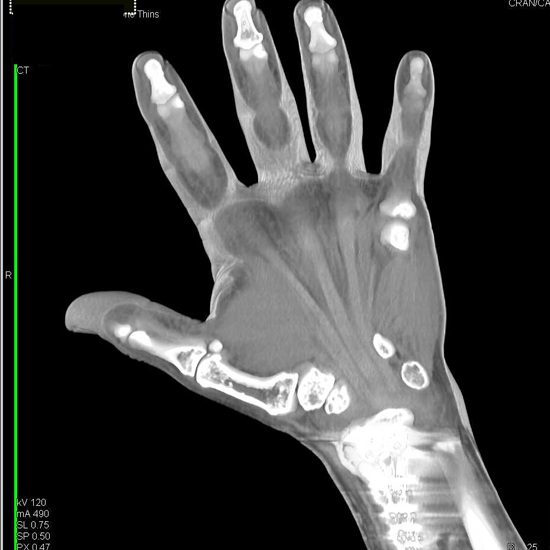

CECT Right Hand is a contrast scan to create a detailed cross-sectional image of the bones and their surrounding soft tissue of the right hand.

A minimum of 4-6 hours of fasting is required for the scan. You need to lie prone on a table and the affected hand is placed above the head in the center of the gantry and another hand is on the side of the body and contrast is injected through IV line then scan is performed.